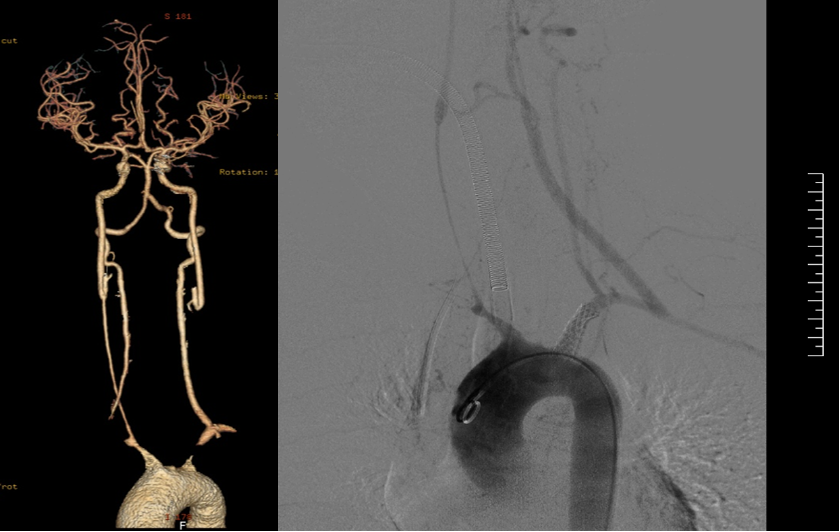

★ 病例2(女性,21岁)

症状:头晕、平衡障碍;ESR 7mm/h, CRP 2.4mg/dl。

诊断:双侧颈总动脉、椎动脉及锁骨下动脉闭塞。

启示:优先腔内重建流入道(如锁骨下动脉),避免开胸创伤;TCD监测脑血流。

前及后循环症状